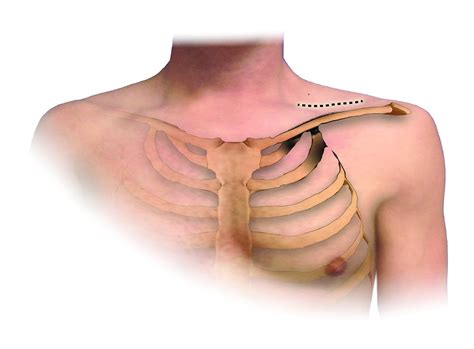

First Rib Resection

This procedure involves removing the first rib to relieve pressure on the nerves and blood vessels. It is often performed for neurogenic and venous TOS. The surgery can be done through a small incision in the neck or under the arm, using either an open or minimally invasive approach.

Scalenectomy involves removing part or all of the scalene muscles, which can compress the brachial plexus. This procedure is typically used for neurogenic TOS and can be performed through a small incision in the neck.

• Incision: The surgeon will make an incision in the neck or under the arm, depending on the approach being used.